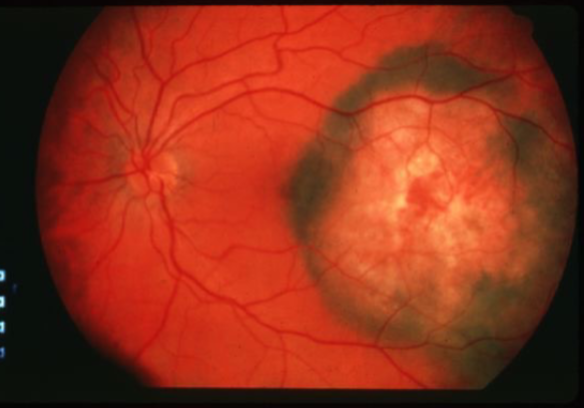

choroidal melanoma

melanoma

melanoma

melanoma

melanoma

melanoma

melanoma

melanoma

melanoma

melanoma

melanoma

melanoma

melanoma

melanoma

melanoma

melanoma

melanoma